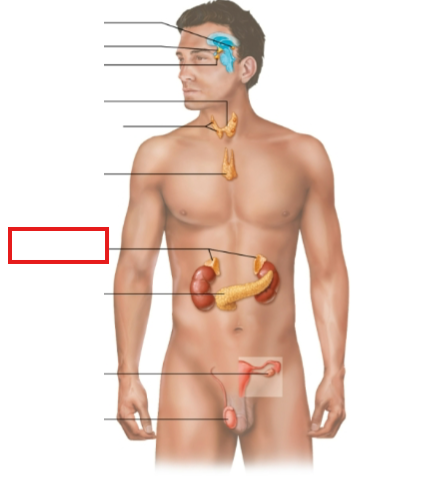

What structure is highlighted?

pineal gland

hypothalamus

pituitary gland

thyroid gland

parathyroid glands

thymus

adrenal glands

pancreas

ovary (female)

testes (male)